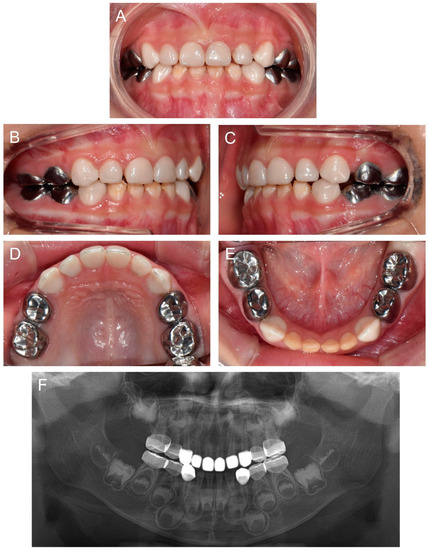

At 2Y9M, full-mouth restoration was performed under outpatient GA (Figure 2). Deciduous molars were treated with stainless steel crowns. Deciduous canines and maxillary anterior teeth were treated with zirconia crowns. Deciduous mandibular anterior teeth were left untreated. At the 3Y11M follow-up (Figure 3), good oral health was maintained, and the anterior open bite was spontaneously corrected with the discontinuance of the finger sucking habit.

Figure 2.

Clinical photos of the proband (IV:3). (A–D) Clinical photos of the proband before the treatment at age 2 years 9 months. (E–H) Clinical photos of the proband after the treatment. The deciduous molars were treated with stainless steel crowns, and the deciduous canines and maxillary anterior teeth were treated with zirconia crowns. The deciduous mandibular anterior teeth were left untreated.